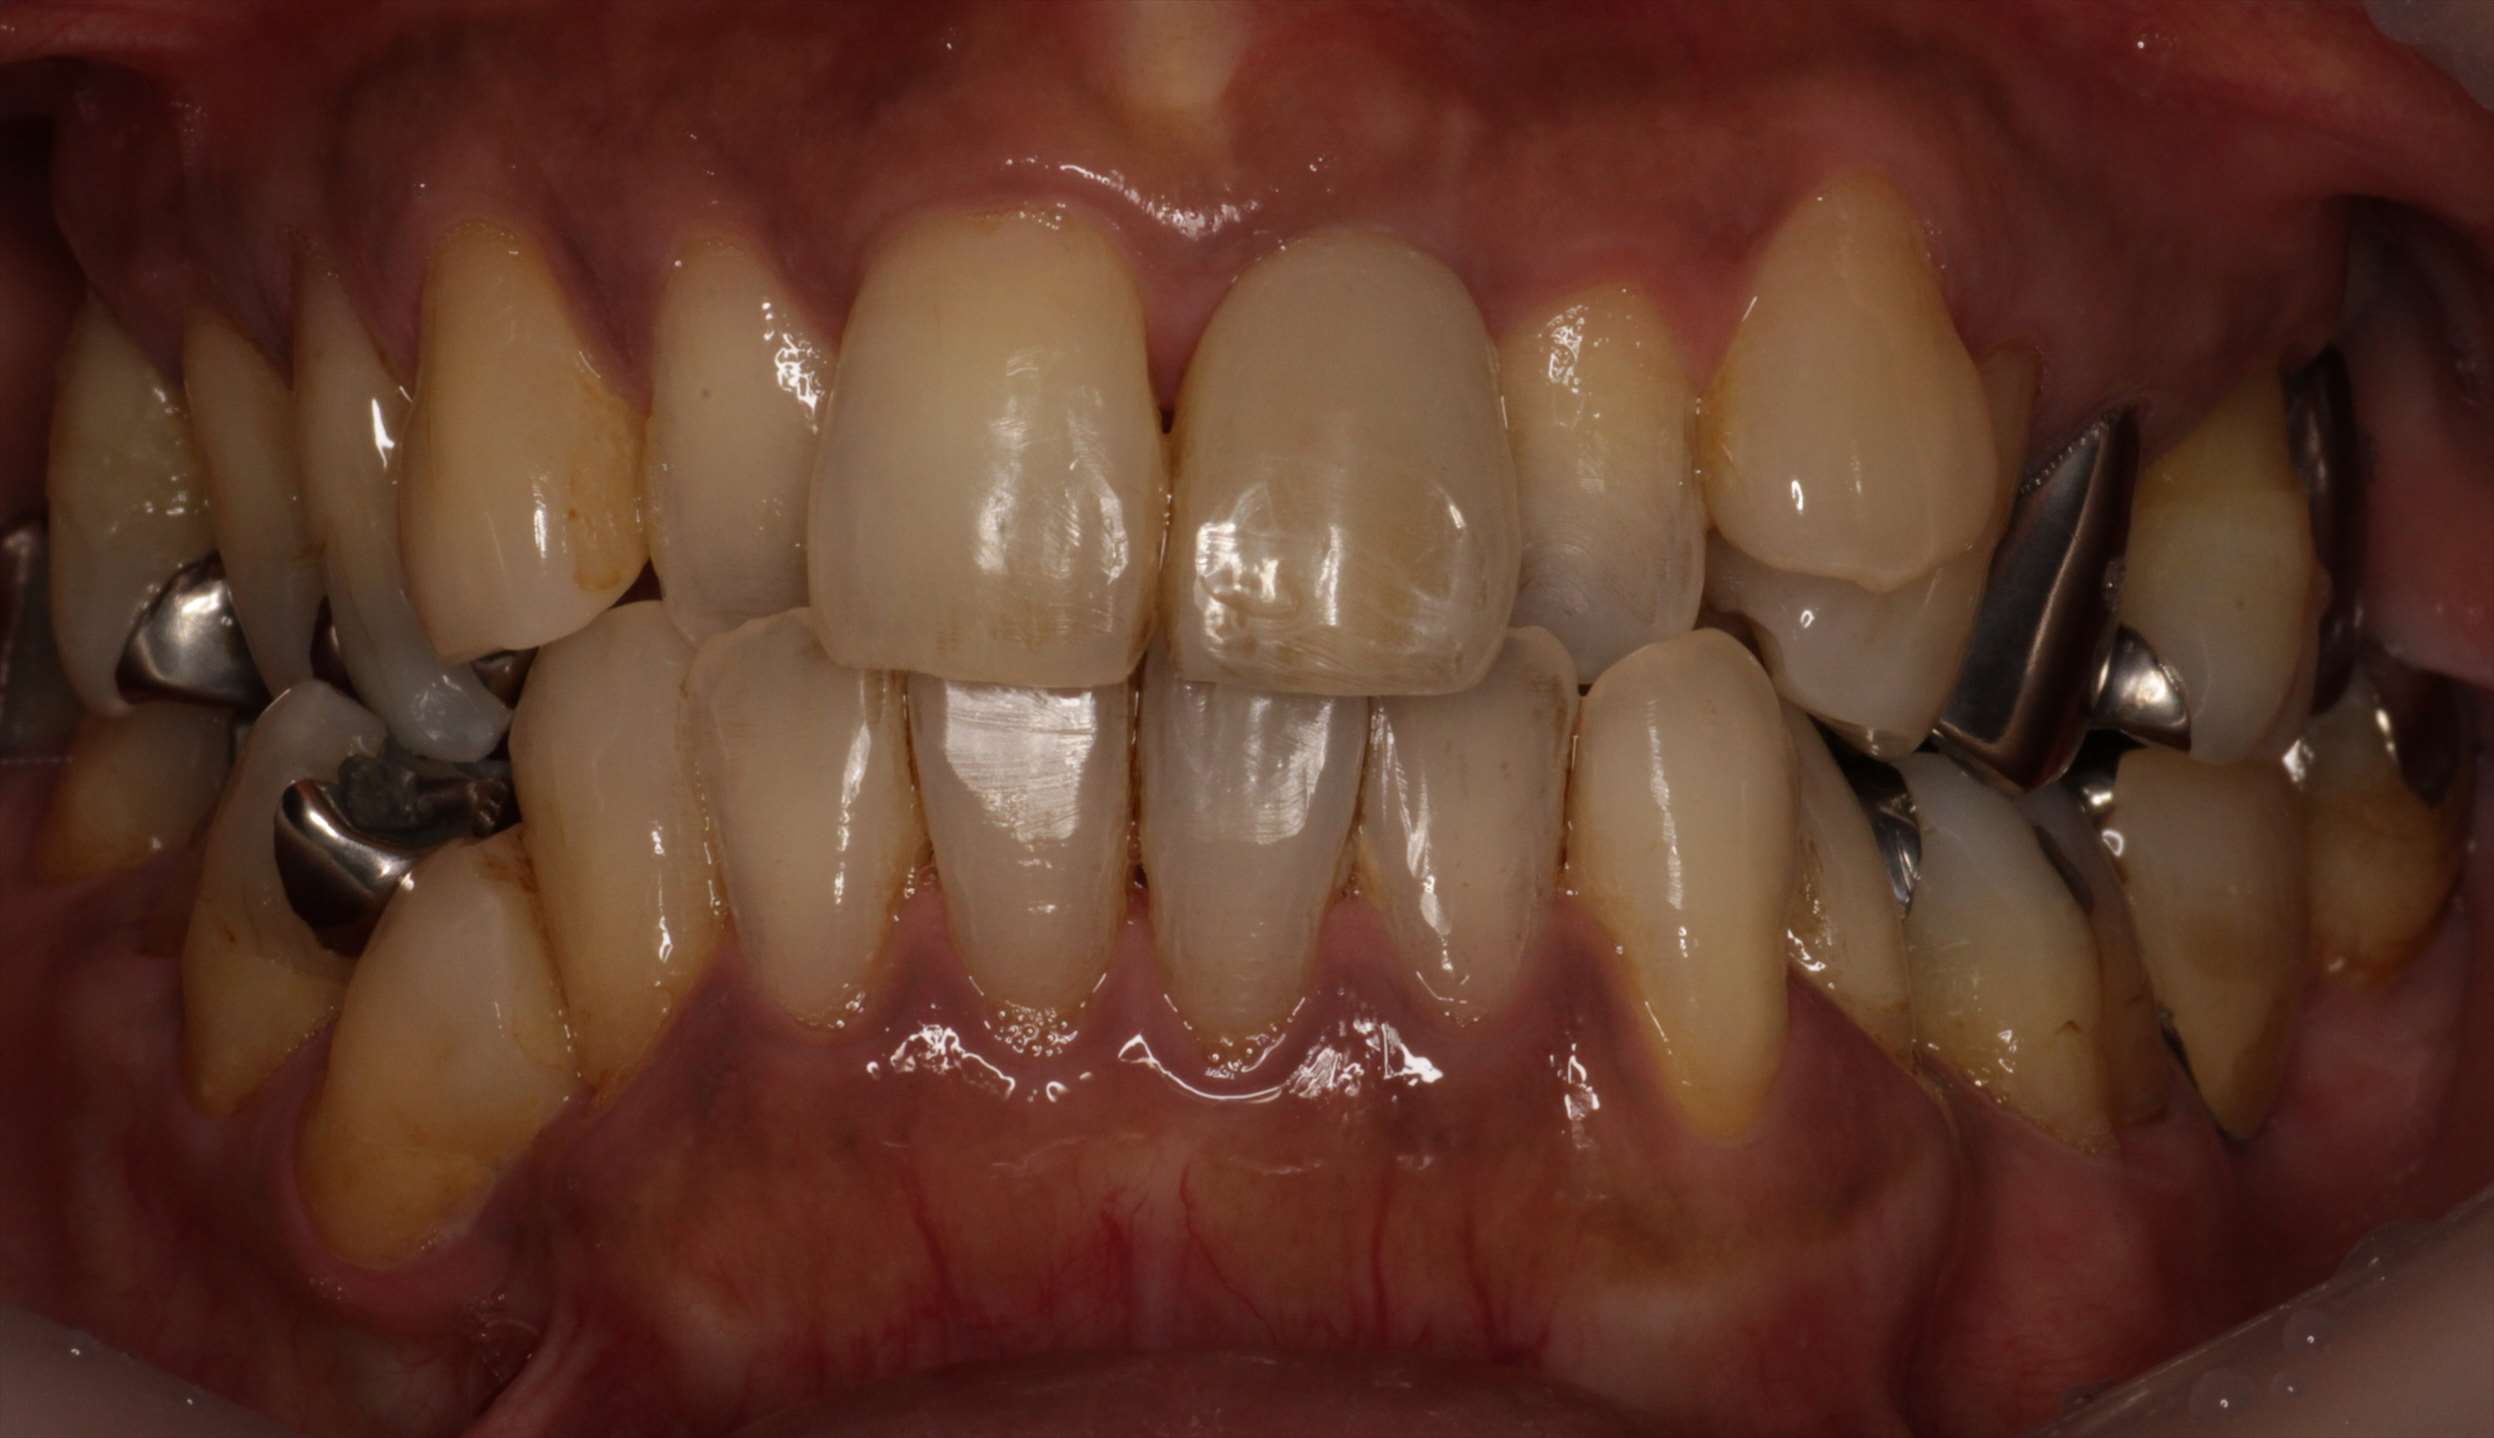

- 治療後